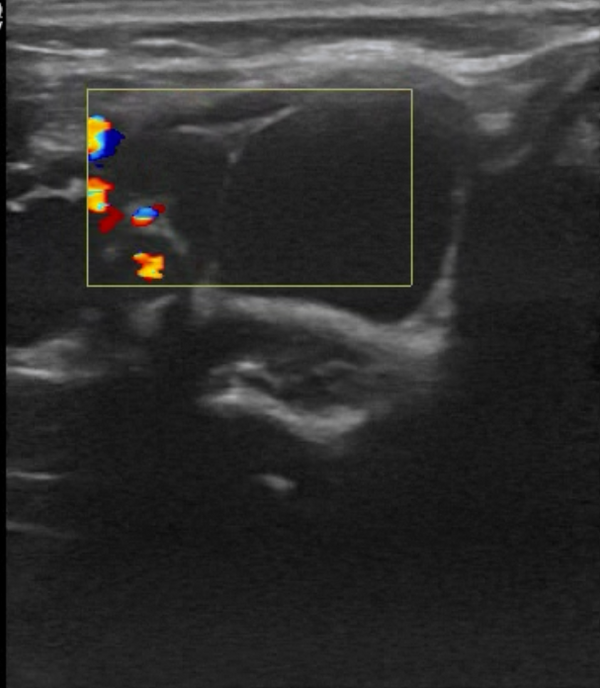

Ультразвуковое исследование: ЛМ классифицируются по данным исследования как макрокистозные, когда отдельные аномальные каналы превышают 10 мм в диаметре, и как микрокистозные, когда отдельные каналы имеют размер менее 10 мм; возможно также сочетание обоих типов. Макрокистозные формы визуализируются как многодольчатые кистозные образования, тогда как микрокистозные очаги выглядят нечёткими и гиперэхогенными из-за множества перегородок между мелкими стенками кист. Микрокистозные формы обычно характеризуются большей инфильтрацией и склонностью к внутренним кровоизлияниям. Смешанные очаги включают как кистозные, так и солидные компоненты, что связано с размером кист и их формой при ультразвуковом исследовании. Цветовое допплеровское картирование позволяет выявлять сосудистые каналы внутри перегородок. В случаях геморрагических или воспалительных осложнений в кистах могут наблюдаться уровни жидкости[6].